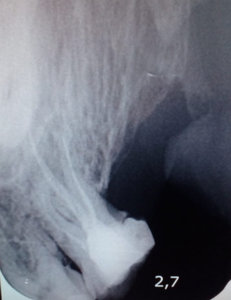

У меня уже месяц болит коренной зуб. Ходил к стоматологу, врач говорит, что нет никаких видимых причин. Мол, зуб целый, ни трещин на нем, ни кариеса, даже фиссурного. Но зуб мучит, особенно при накусывании. К вечеру усиливается. Я регулярно слежу за гигиеной полости рта, поэтому недоумеваю, что является причиной боли коренного зуба. Как определить причину? Может, нужно снимок сделать?

Добрый день, Илья! Безусловно необходимо сделать снимок! Я рекомендую не откладывать это надолго, потому как, скорее всего, речь идет о пульпите (характерная приступообразная боль, которая усиливается в ночное время, при накусывании), который может осложниться периодонтитом, и вероятность успешного лечения в разы снизится.

Терпеть зубную боль не стоит, Вам следует как можно скорее посетить врача-стоматолога, он установит причину и если потребуется начнет лечение. Заключается оно в тщательном депульпировании корневых каналов. Успехов!